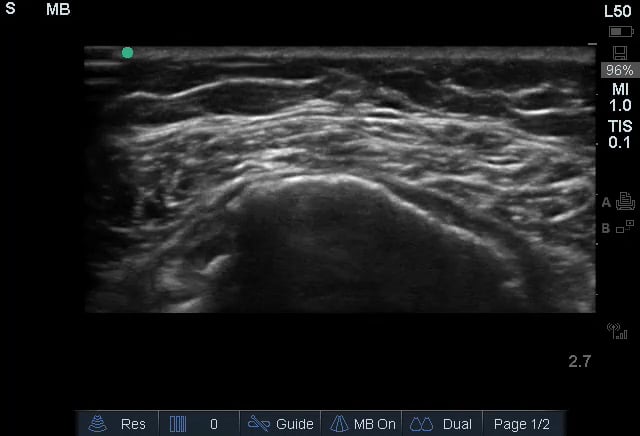

A rotator cuff tear is a common musculoskeletal (MSK) injury involving one or more of the four tendons surrounding the shoulder joint. These tears can range from partial to full-thickness and are a significant cause of shoulder pain and weakness, often resulting from acute trauma or chronic degeneration. In medical imaging, ultrasound is a valuable tool for diagnosing rotator cuff tears due to its real-time capabilities and ability to visualize soft tissue structures.

Ultrasound allows for dynamic assessment of the rotator cuff, identifying fluid collections, tendon retraction, and changes in echotexture that indicate a tear. Early and accurate diagnosis via ultrasound guides treatment decisions, from conservative management to surgical repair, improving patient outcomes and aiding rehabilitation in MSK practice.